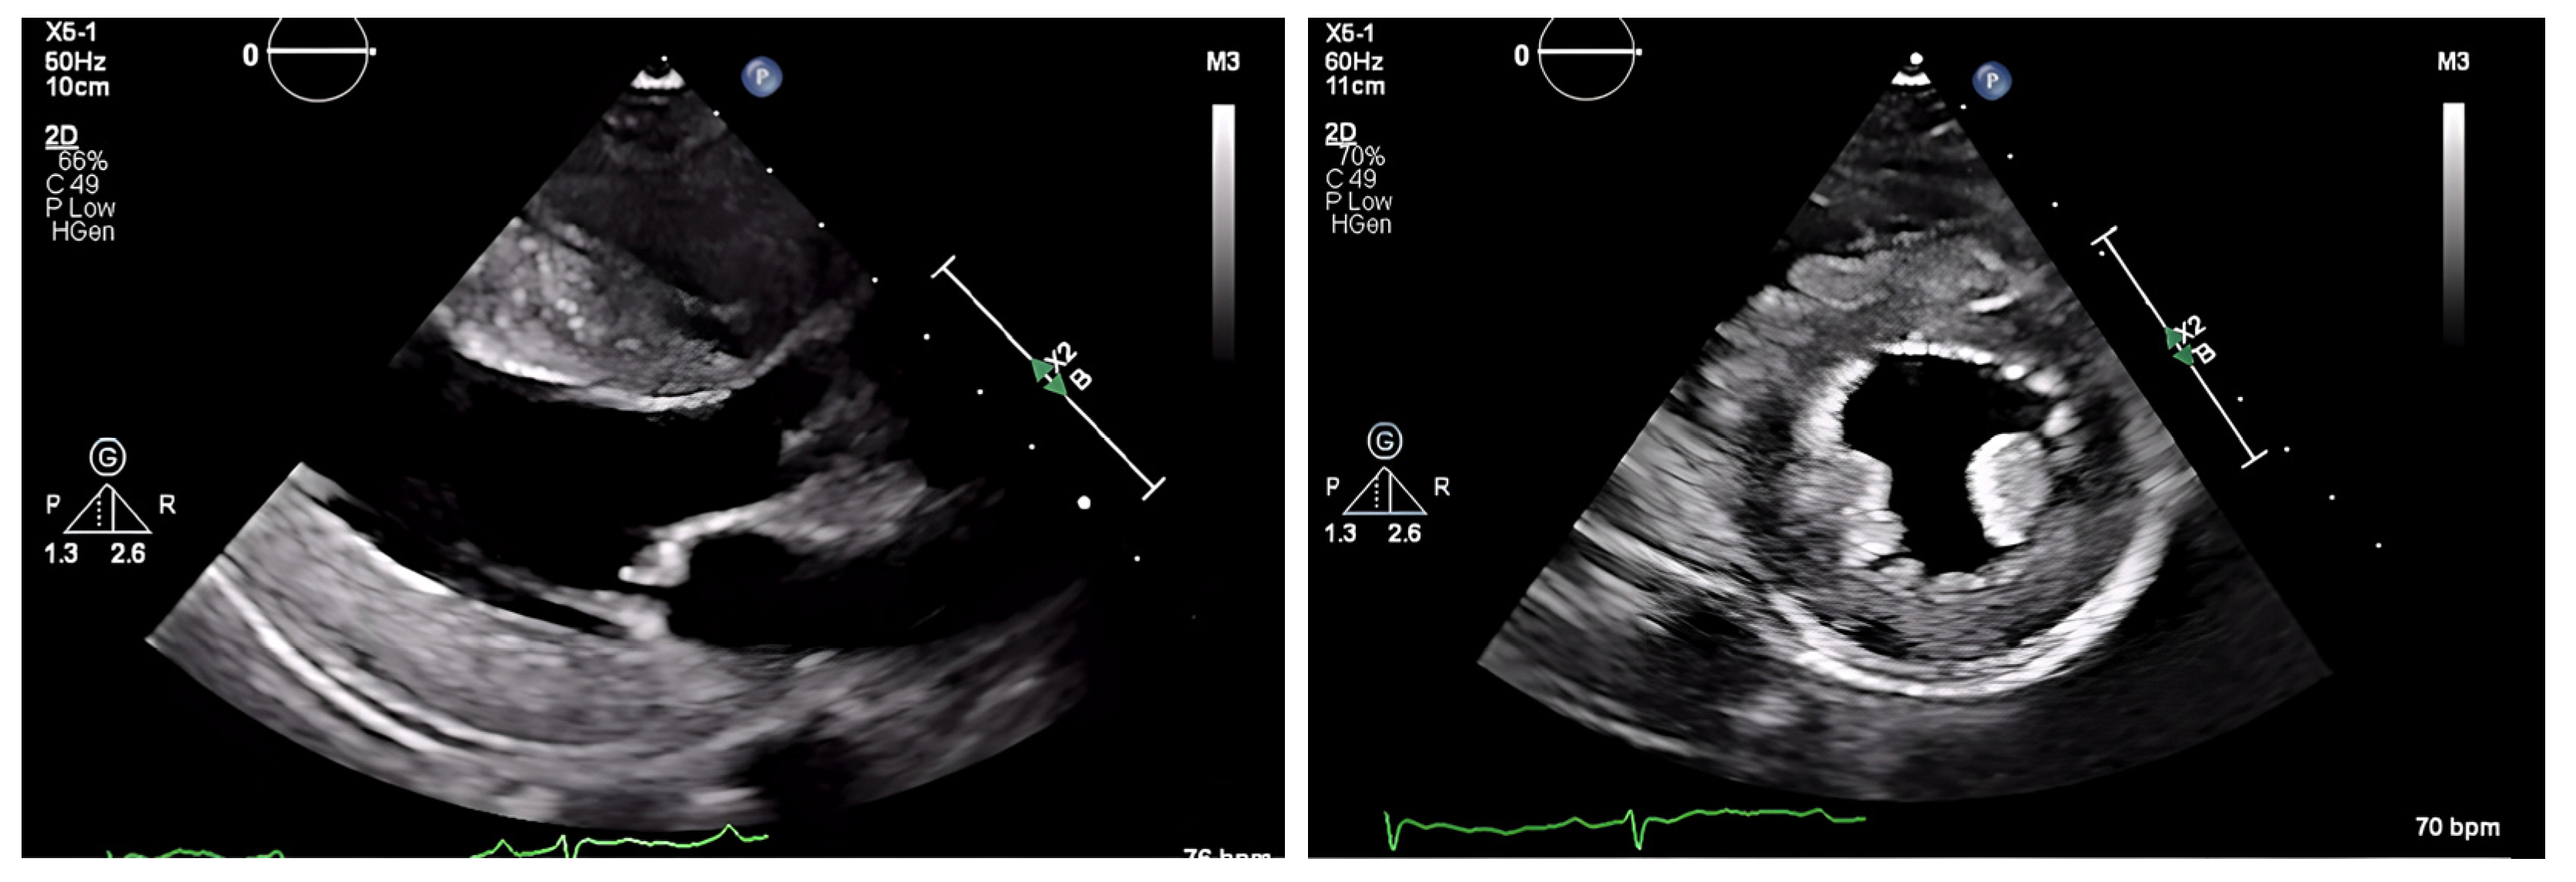

The chest radiograph did not show any acute findings. Electrocardiogram (ECG) (Figure 1) showed normal sinus rhythm with first-degree atrioventricular block, left axis deviation, and low voltage in limb leads. No prior echocardiogram (ECHO) was available, so an initial ECHO was obtained showing preserved ventricular ejection fraction (EF), moderate left ventricular hypertrophy (LVH), stage II diastolic dysfunction, and small pericardial effusion (Figure 2 and Figure 3).

One of the first clues of suspected CA is the EKG. A characteristic ECG finding in CA is low voltage QRS in all limb leads (as amyloid fibrils are electrically silent) and poor R wave progression or a pseudoinfarct pattern with Q waves in precordial leads [32]. This is incongruent with the typical finding of ventricular thickening seen on echocardiography (ECHO). However, with only 30–70% of patients meeting low voltage criteria on EKG, its absence cannot preclude a diagnosis of CA [2]. Other common ECG findings are AF, intraventricular conduction delays, various atrioventricular blocks, and bundle branch blocks.

Figure 1. ECG showing normal sinus rhythm with first-degree atrioventricular block and left axis deviation.